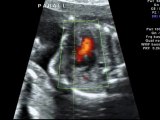

Sospetta trasposizione dei grossi vasi

Trasposizione corretta dei grossi vasi

Trasposizione completa dei grossi vasi